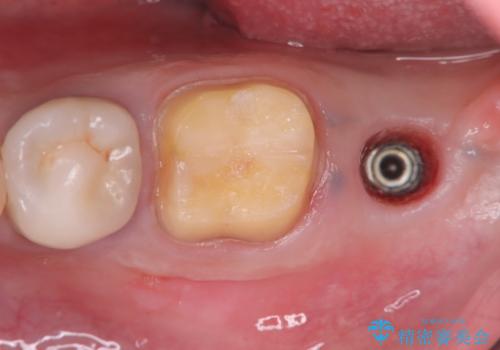

- 過去にヘミセクションが行われていたと思われる左下7番は、大きな歯根嚢胞および根尖病変が認められ、さらに骨縁下カリエスを伴っており、歯肉には瘻孔が形成されている状態でした。

保存は困難と判断し、左下7番は抜歯即時インプラントによる治療を行いました。